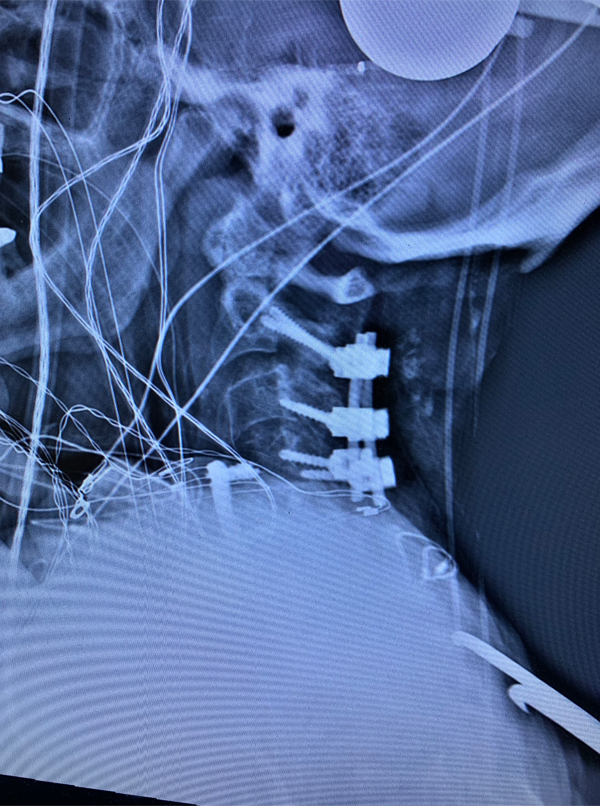

Figures 2a, b, c: Preoperative sagittal CT scans of the cervical spine demonstrating preoperative instrumentation. Note degenerative changes and anteriolisthesis of C2 and C3.